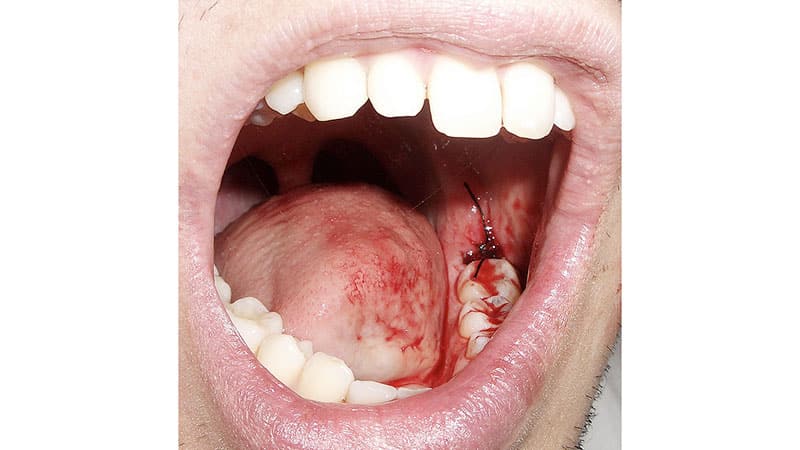

Процедура проводится с использованием мощных обезболивающих в условиях хирургического кабинета. Все необходимые антисептические меры обеспечивают стерильность помещения. Через три дня после операции рану зашивают рассасывающимися нитями, которые удаляются только после полного заживления.

Средняя продолжительность процедуры составляет от 30 до 60 минут. Если требуется удалить как минимум два зуба мудрости, то каждую операцию рекомендуется проводить с интервалом в три недели. Лечение других зубов, включая их чистку и пломбирование, можно начинать через 2–4 недели после основной операции.

Несмотря на современные технологии, применяемые в стоматологии, для предотвращения осложнений после удаления зуба мудрости (нижней челюсти) важно пройти полный курс восстановления. Время реабилитации может варьироваться, так как оно зависит от индивидуальных особенностей организма.